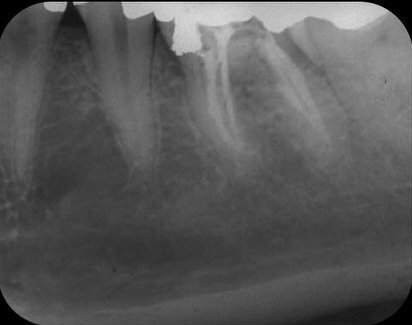

Als jonge tandarts was ik volkomen ontdaan over deze iatrogene complicatie. Er waren in 1982 geen speciale cementen beschikbaar om een perforatie te sluiten, en dus besloot ik om het defect tijdelijk af te sluiten met amalgaam. De twee mesiale en twee distale kanalen werden met handvijlen geprepareerd, en de kanalen werden geïrrigeerd met 2,5% natriumhypochloriet. Daarna vulde ik de kanalen door middel van laterale condensatie met gutta-percha en AH26, waarbij in het distolinguale kanaal ruimte werd gemaakt voor een wortelstift (afb. 3). Volgens de toen geldende inzichten was een gegoten opbouw geïndiceerd alvorens er een volledige gouden kroon geplaatst zou worden.

Afb. 3: Kanaalvulling aanbracht en perforatie afgesloten met amalgaam